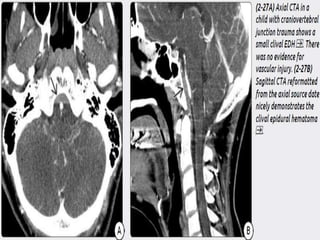

Clival EDH- develops d/t hyperflexion or

hyperextension injury to the neck and are possibly

caused by stripping of the tectorial membrane from

attachments to the clivus. Less commonly with skull

base #.

Mostly occurs in children and often presents with

multiple cranial neuropathies. 6Th nerve is most

commonly involved.

Typically limited in size by tight junction of dura to

basisphenoid and tentotrium.

Tx – pt with clival EDH with minor cranal nerve invol

need Cervical collar.

CT- hyperdense collection betweenclivus and tentorial

membrane, anterior to medulla.